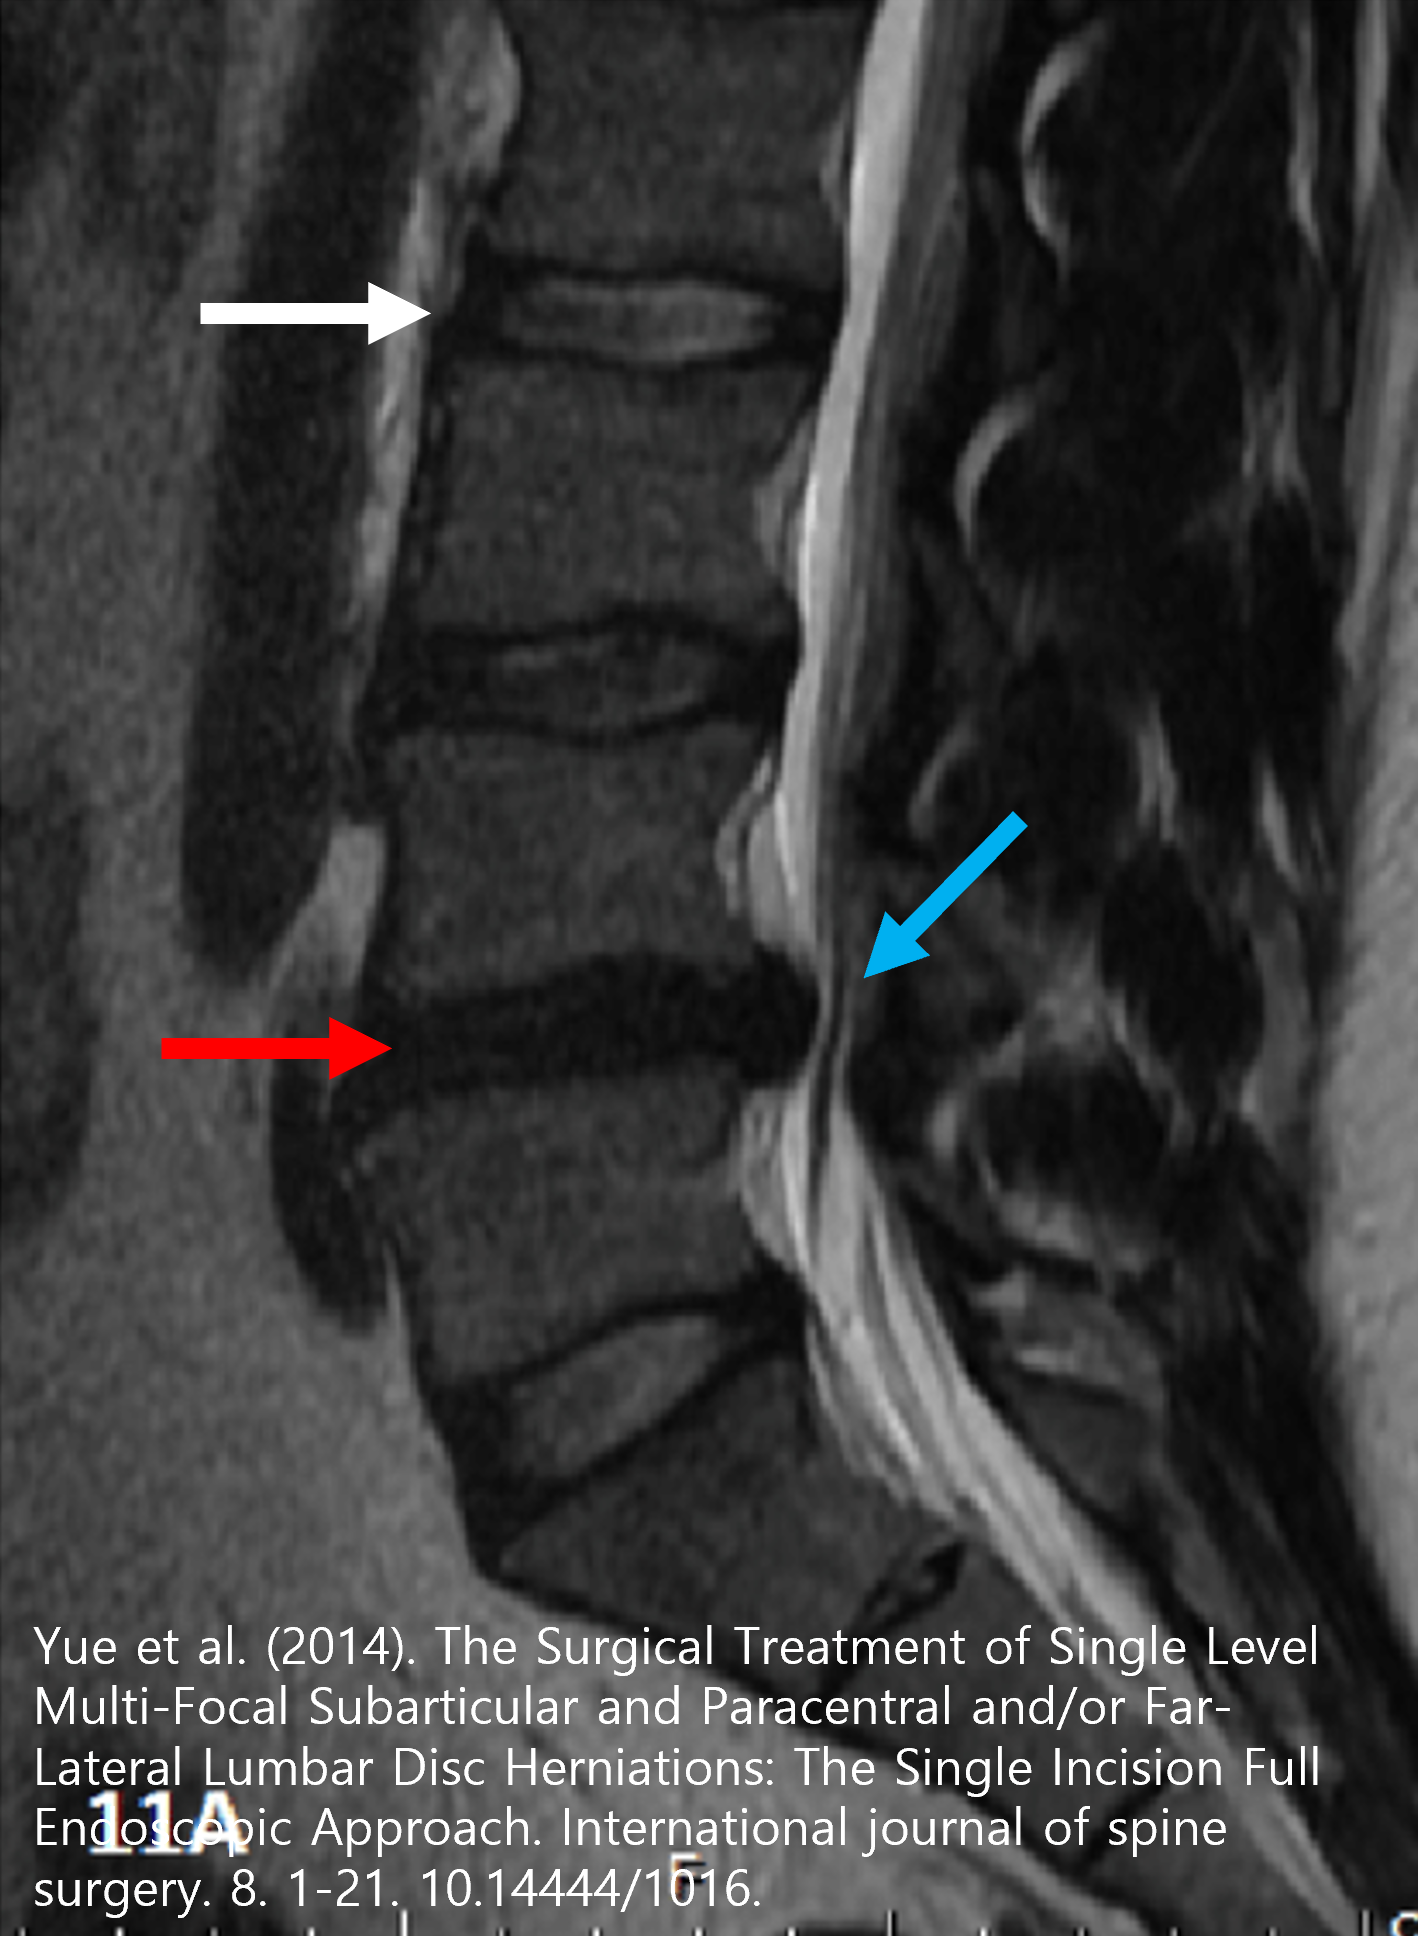

앞서 말씀드린대로 디스크를 조성하는 물질들은 대부분 물분자와 콜라겐, 다당류 조직이기 때문에 MRI를 통해서만 그 형태를 정확하게 파악할 수 있습니다. 아울러 고른 신호강도를 보여야하는 척추신경이, 파열된 디스크로 인해 눌릴 경우 신호가 바뀌는, '척수병증' 이라는 심각한 질환을 유일하게 진단 할 수 있는 검사이기도 합니다.

위 MRI 영상을 보시면 정상적인 디스크의 내부는 (하얀 화살표) 수분으로 인한 높은 신호강도를 보여 하얗게 보여야 하지만, 손상된 디스크의 내부는 (붉은 화살표) 수핵이 후방으로 탈출된 후 흡수가 되어 수분이 없어 저신호강도로 검은색으로 보이게 됩니다. 후방으로 탈출된 디스크 조직 (파란 화살표)는 척추체 후방에 위치한 척추신경을 압박하여 신경증상을 일으키게 됩니다.